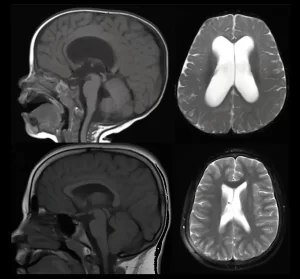

Conheça um pouco mais do blog informativo do neurocirurgião Dr. Diego Ramos. Tópicos sobre escoliose, neucirurgia adulta e pediátrica são abordados para trazer um pouco de conhecimento para pacientes ao redor do mundo.